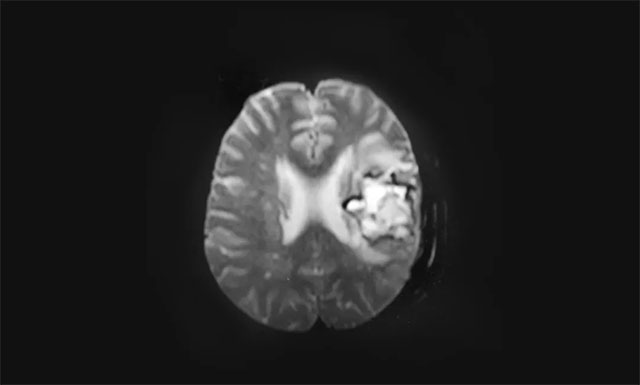

▲ 術(shù)后影像顯示左側(cè)額骨骨質(zhì)不連續(xù),毗鄰皮下軟組織稍腫脹,呈術(shù)后改變

入院后,完善患者各項(xiàng)檢查,發(fā)現(xiàn)患者不能言語,右側(cè)肢體肌力為1級,肌張力增高。